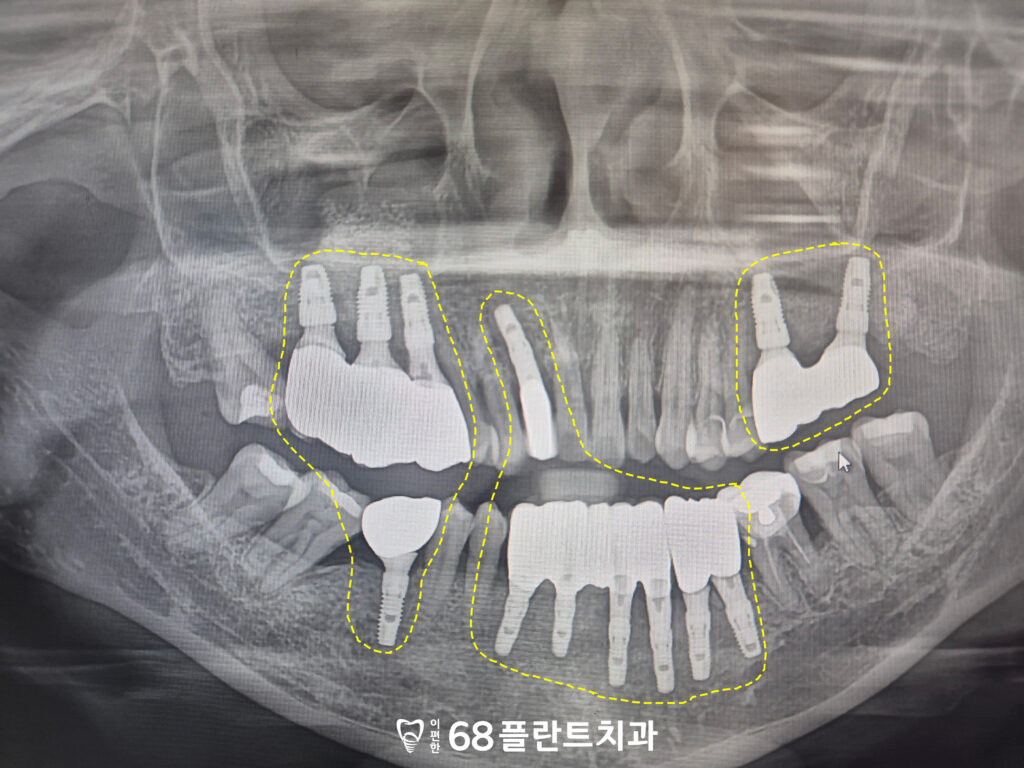

25.11.25

먼저 어금니를 발치한 후

상악동거상술 및 뼈이식을 동반하여

임플란트를 식립하고,

치유기간을 거친 뒤 보철 작업을 진행하여

상실된 치아의 기능을

회복시켰습니다.

임플란트가 안정적으로 자리잡을 수 있도록

치유기간 동안 충분히 뼈와

결합할 수 있는 시간을 제공했으며,

그 후 보철물을 장착하여

자연스러운 치아 모양과 기능을

회복할 수 있었습니다.

이후 어금니가 완성된 후

앞니도 치료를 진행하였습니다.